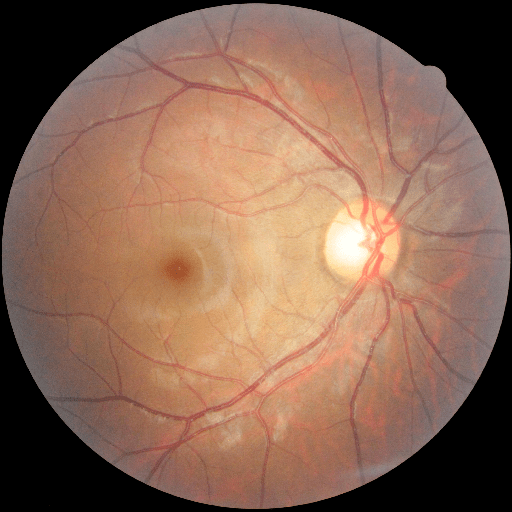

We conducted a case study on diagnosing diabetic retinopathy with ensembles of DL models. For benchmarking the performance of our ensemble-based solutions under the scheme described in Sec.3.3, we used two popular collections of diabetic retinopathy image data, the Kaggle Diabetic Retinopathy dataset [22] (hereafter referred to as “Kaggle-DR”) and the Messidor-2 dataset [23], each respectively consisting of and high resolution images. Diabetic retinopathy is graded into five SLs, as displayed in Figure 2. Following the problem setup used in previous papers [24], we trained models to distinguish the referable (SL2-4) cases from the non-referable ones (SL0 & SL1) (see Section B.1 for more detailed descriptions). We also tested our trained ensemble models on two o.o.d. image datasets (ImageNet [25] and CIFAR-10 [26]) to examine their capabilities of identifying o.o.d. inputs (see Section B in the supplementary materials).

The Kaggle-DR dataset comprises high resolution images. The presence of diabetic retinopathy is rated into five different SLs: no-DR (SL0), mild (SL1), moderate (SL2), severe (SL3), and proliferate (SL4), as illustrated in Figure 2. We divided the Kaggle-DR dataset into a development set and a test set, which respectively consisted of and images. The data in the development set were used to train and validate our Deep Learning (DL) models. The Messidor-2 dataset [38] that consisted of images was also used in our experiment as an additional dataset to test the true generalization performance of the models trained on the Kaggle-DR dataset. Images in Messidor-2 dataset were graded into the five SLs as in the Kaggle-DR dataset. Figure S.1 provides an illustration of the datasets used in our experiments.